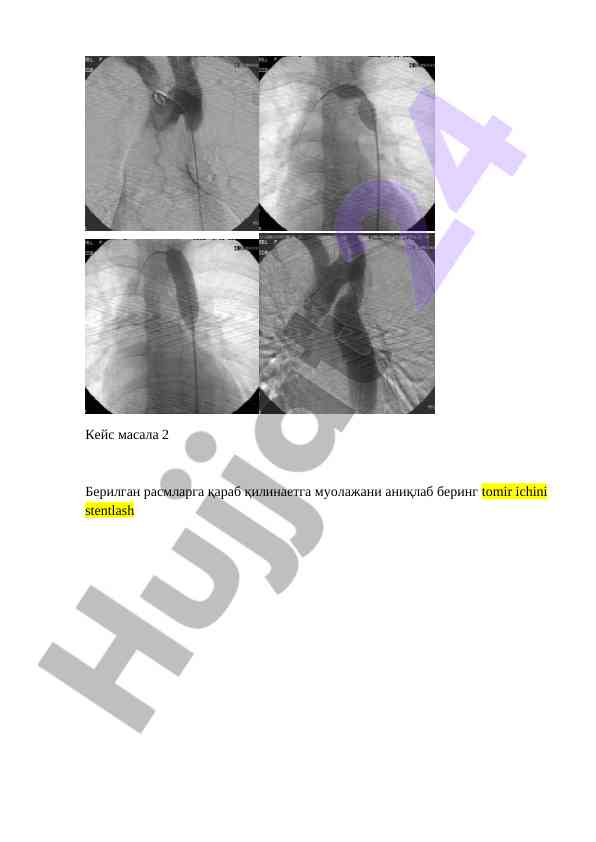

Эндоваскуляр хирургия ва диагностика бўйича саволлар ва учрашувлар, томирларнинг паталогияси, эндоваскуляр текширувлар бўйича аниқлаш ва муолажалар.